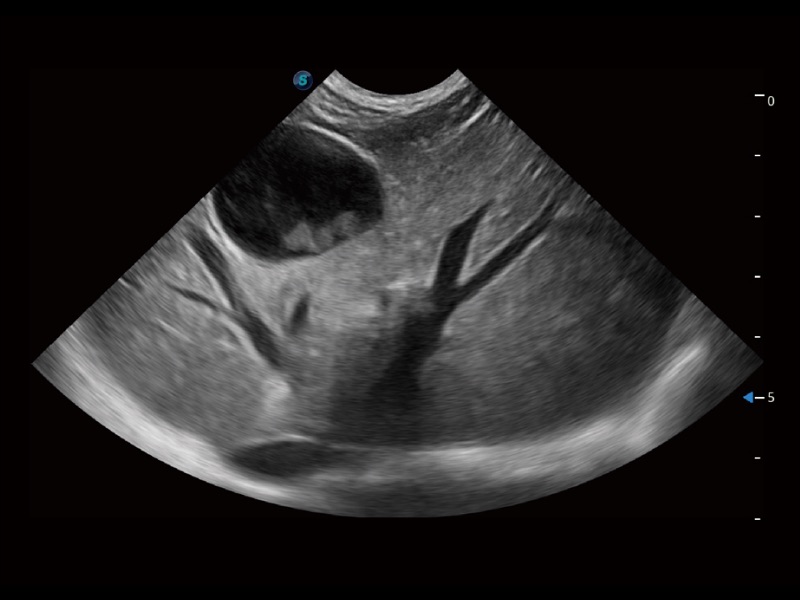

大型犬、马科、农场动物及大型异宠动物

为精细结构及组织边缘提供高清晰度的图像和更大的成像视野。帮助减轻医生的用眼疲劳,快速精准获得测量的数据。